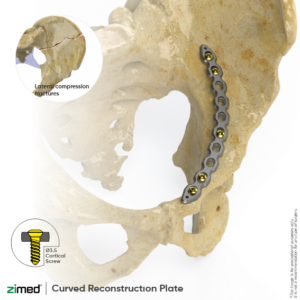

Curved Reconstruction Plates